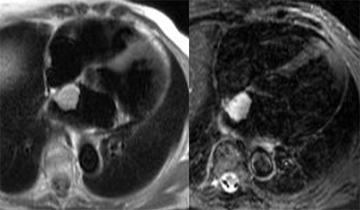

– Insuffisance aortique : recherche de bicuspidie et quantification de la fraction de régurgitation par l’IRM sont fiables.

– Rétrécissement aortique : Recherche de bicuspidie fiable, possibilité de quantification de la surface valvulaire et du gradient systolique.